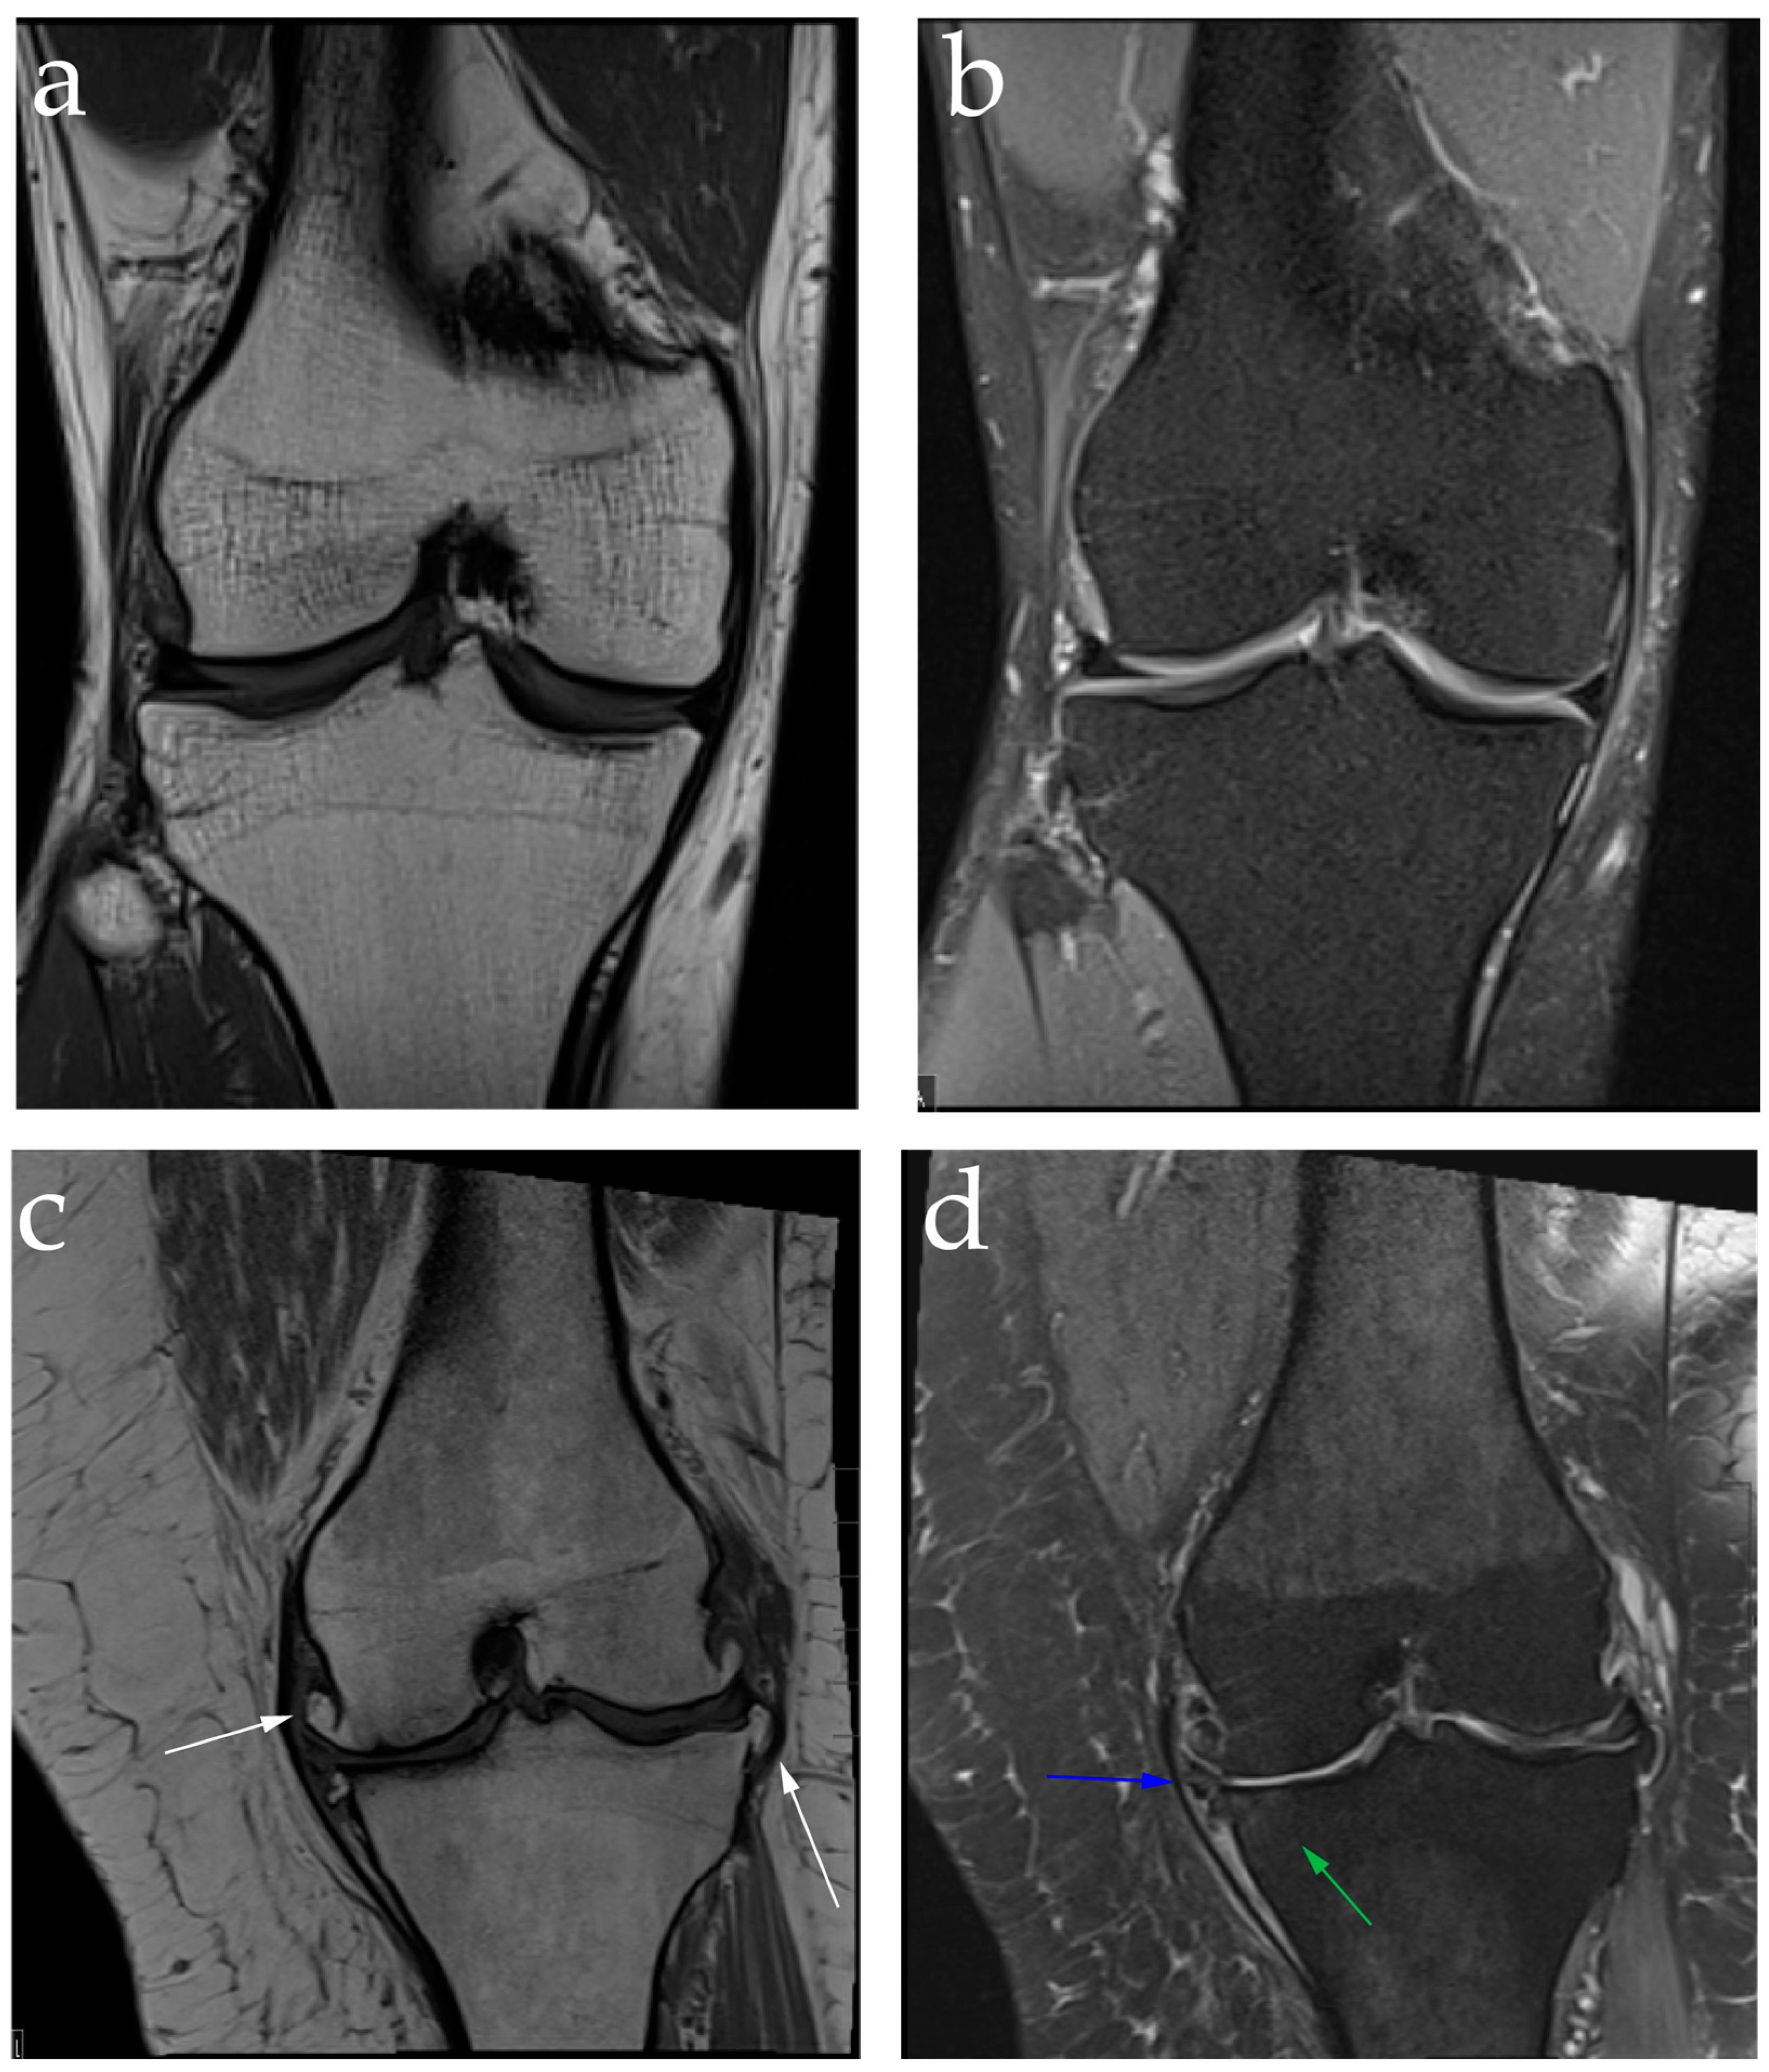

2.2. Diagnosis: Clinical Features and Image Findings

7.3. Genicular Artery Embolization Technique